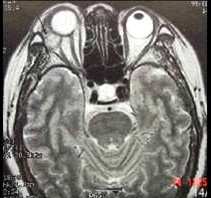

(如图)该种疾病的病因可能是由于()

-

(如图)该疾病的说法正确的是()